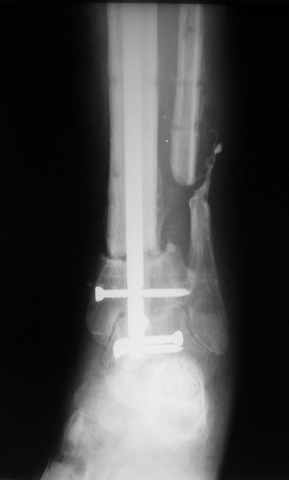

Ерсин, мы тоже имеем опыт такой фиксации. Подобную операцию за последние 3 года мы сделали трем пациентам. Снимки одного из них я прилагаю.

К сожалению, ни в одном из этих 3-х случаев мы не получили удовлетворяющего нас результата. Очень трудно провести штифт, введенный антеградно ровно по центру таранной кости. Отсутствие подвижности между диафизом и дистальным отломком большеберцовой кости (после фиксации в аппарате в течение 1-2 мес) очень усложняет проведение штифта в центр блока таранной кости. Поэтому мы от этого пока отказались, и проводим штифт через пятку. При данном варианте фиксации подобных проблем не возникало ни разу.